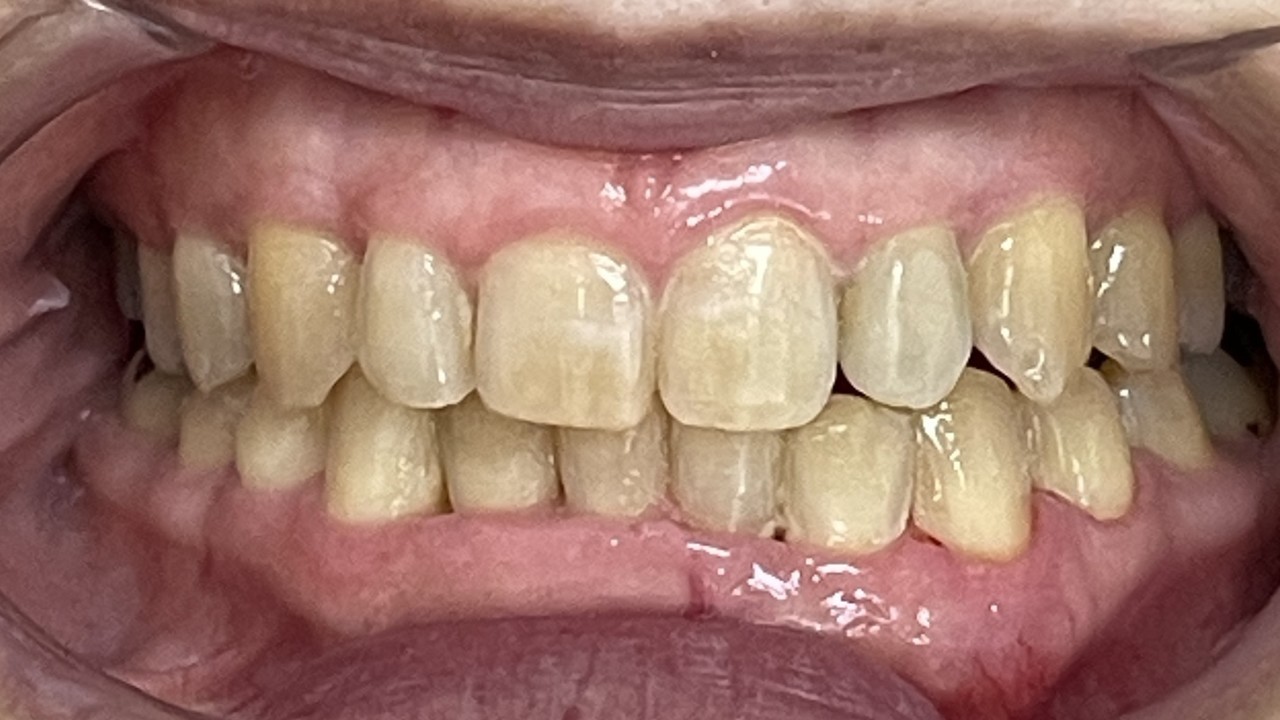

Before

After

矯正の種類 / invisalign GO

年齢・性別 / 30代女性

主訴  /  叢生 かみ合わせ

治療期間 / 17ヶ月

費用 / 簡易検査 5,000円(税別) 精密検査 30,000円(税別)

両額マウスピース 450,000円(税別)  両額リテイナー料 60,000円(税別)

※マウスピース交換時別途調節料3,000円(税別)

副作用 / 口内炎・歯の移動に伴う痛み・知覚過敏 ※数日で収まる場合が多いです

リスク / 後戻り防止の為、夜のみマウスピースで保定を指示